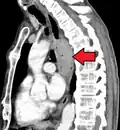

Esophageal cancer (lower part) as a result of Barrettʼs esophagus

Male predominance is particularly strong in esophageal adenocarcinoma, occurring about 7 to 10 times more frequently in men.[26] This imbalance may be related to the characteristics and interactions of other known risk factors, including acid reflux and obesity.[26]